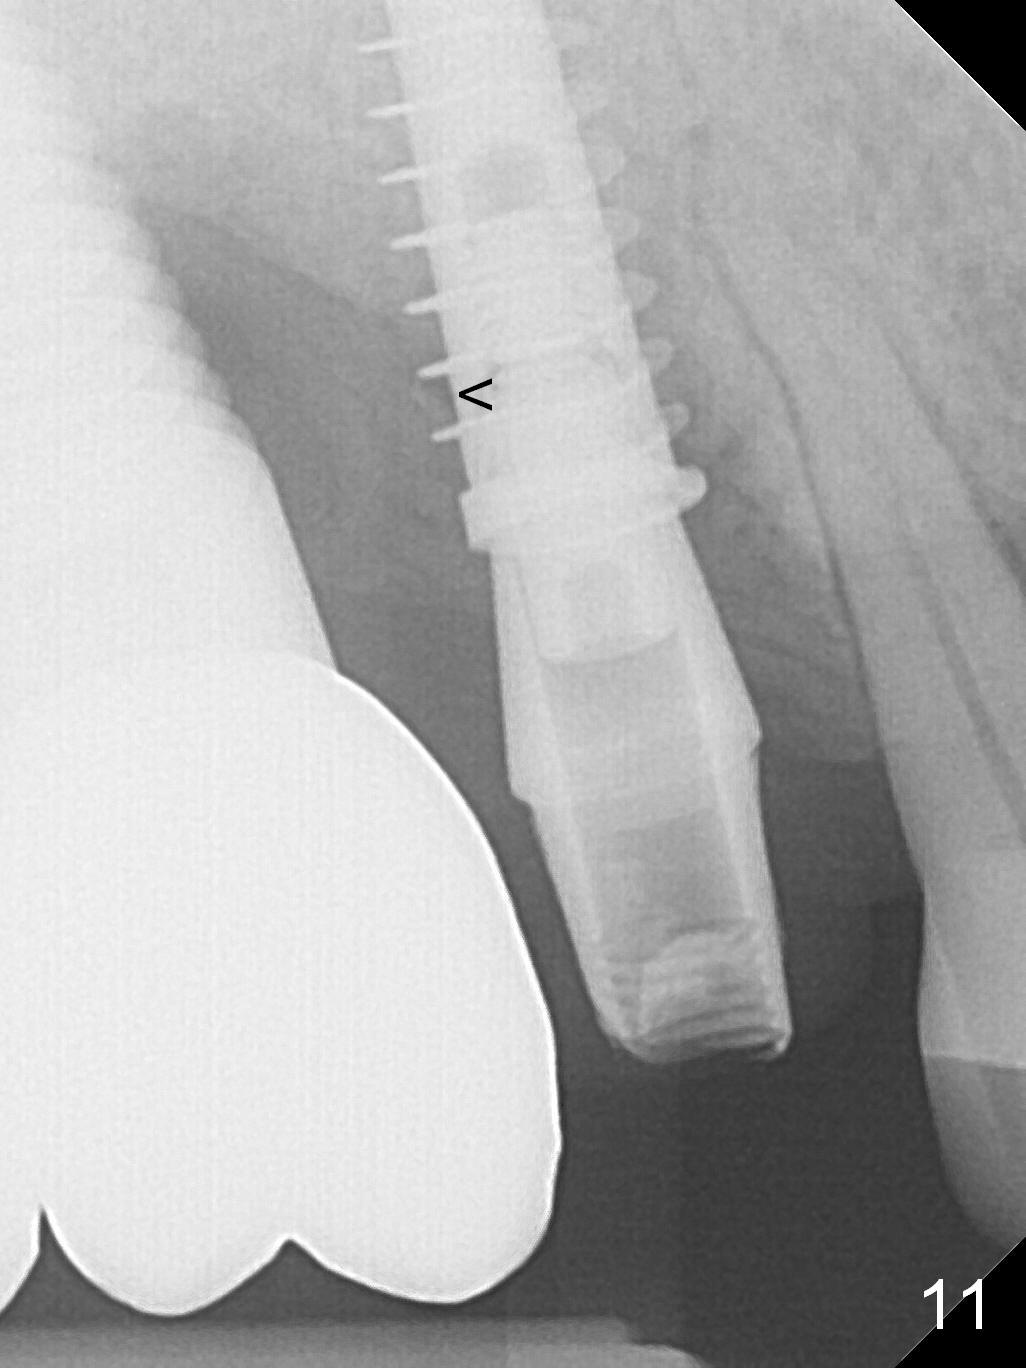

The distal papilla reforms buccally (Fig.8 *) and palatally (Fig.9) 4 months postop.  It appears that the 4 mm cuff of the pair abutment (Fig.10 >) is apical to the mesial crest (*).  The distal coronal implant threads seem to be covered by bone graft (Fig.11 <).  Therefore pair abutments with 5 mm or more cuff are required in cases of the uneven bone.   Implants have to be placed deep.  CT taken 3 months post cementation (10 months postop) shows that the implant is placed in the middle of the alveolus without apparent thread exposure.  CT taken 1 year and 8 months post cementation (Fig.13) shows that the implant is placed in the middle of the alveolus without apparent thread exposure, as compared to those at #2 and 3, which are placed buccal (B).